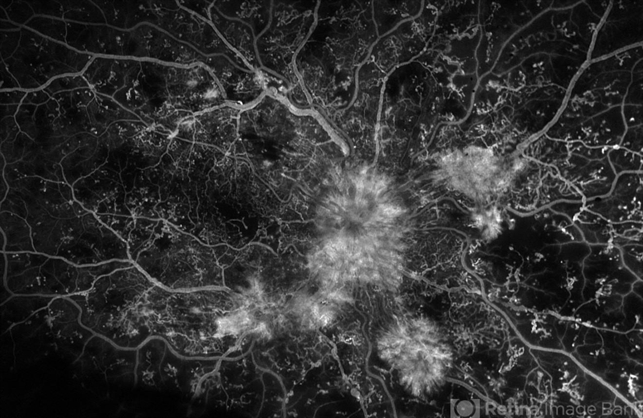

By Kyle D Kovacs, MD

Weill Cornell Ophthalmology

Co-author(s): Tamara Lenis - Uploaded on Jan 20, 2022.

- proliferative diabetic retinopathy (PDR), ischemic CRVO, COVID-19

- Imaging device

- Optos Silverstone

- Fluorescein angiogram of 21 year-old male with Type 1 DM, with new diagnosis of PDR and CRVO 6 months following hospitalization for DKA and COVID-19 pneumonia, noted acute deterioration in vision during hospitalization. Bilateral non-perfusion and florid neovascularization.